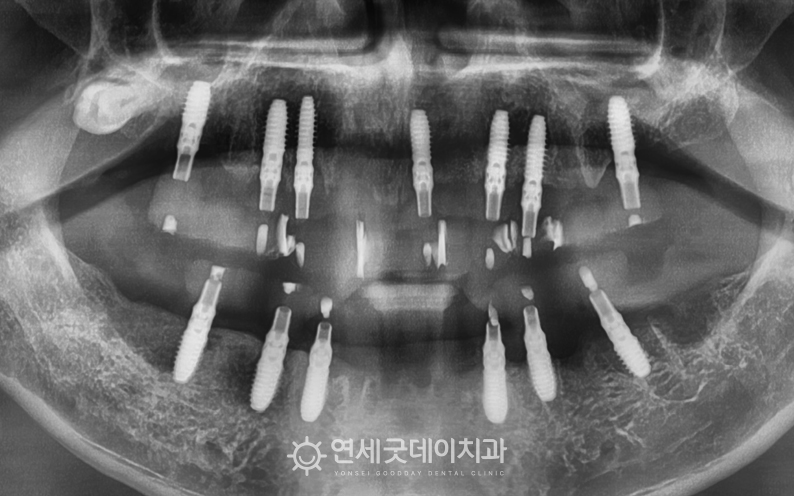

환자분은 중등도 이상의 치주질환으로 인해 이로 인해 치아 배열이 불규칙해지고

엑스레이 상에서도 상하악 모두 이 밖에도 좌우 어금니가 상실되었고

앞니 일부는 크라운으로 수복된 상태였으며 또한 잔존치의 예후도 좋지 않았기 때문에

잔존치 발치와 동시에 임플란트 뼈이식과